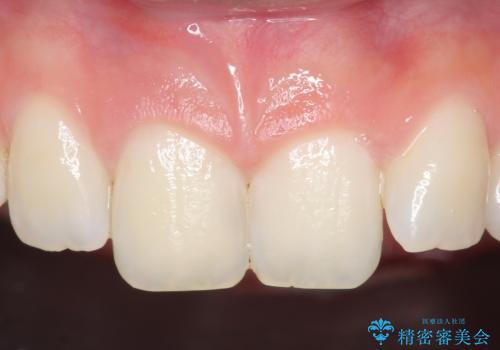

オールセラミッククラウン 痛みの引かない歯の治療

- 他院にて根管治療を行っていたが、痛みが引かないので診て欲しいといらっしゃった方の症例です。

マイクロスコープ下でラバーダムを使用しながら根管治療を行い、痛みが治まった後にオールセラミッククラウンによる補綴を行いました。

今回用いたオールセラミッククラウンはジルコニアフレームという白い素材の上にセラミックを盛っているため、審美性が非常に高いのが特徴です。